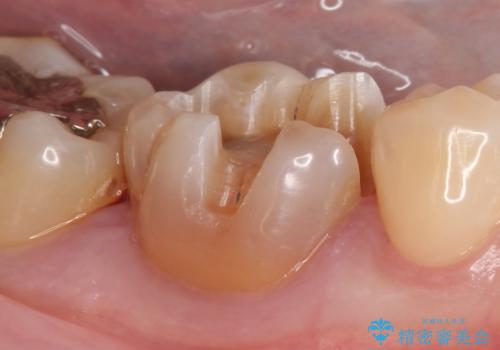

- 右下6番目の歯の舌側に虫歯があるので治療して欲しいといらっしゃった方の症例です。

古い銀歯及び虫歯を除去後、セラミックインレーにて修復を行いました。

当院のセラミックインレーはemaxという強度と審美性に優れた材料を使用しています。

またプレス方式でインレーを製作しているため、削り出しで製作するCADCAMより優れた適合性も持ち合わせており、虫歯が再発しにくい修復物です。